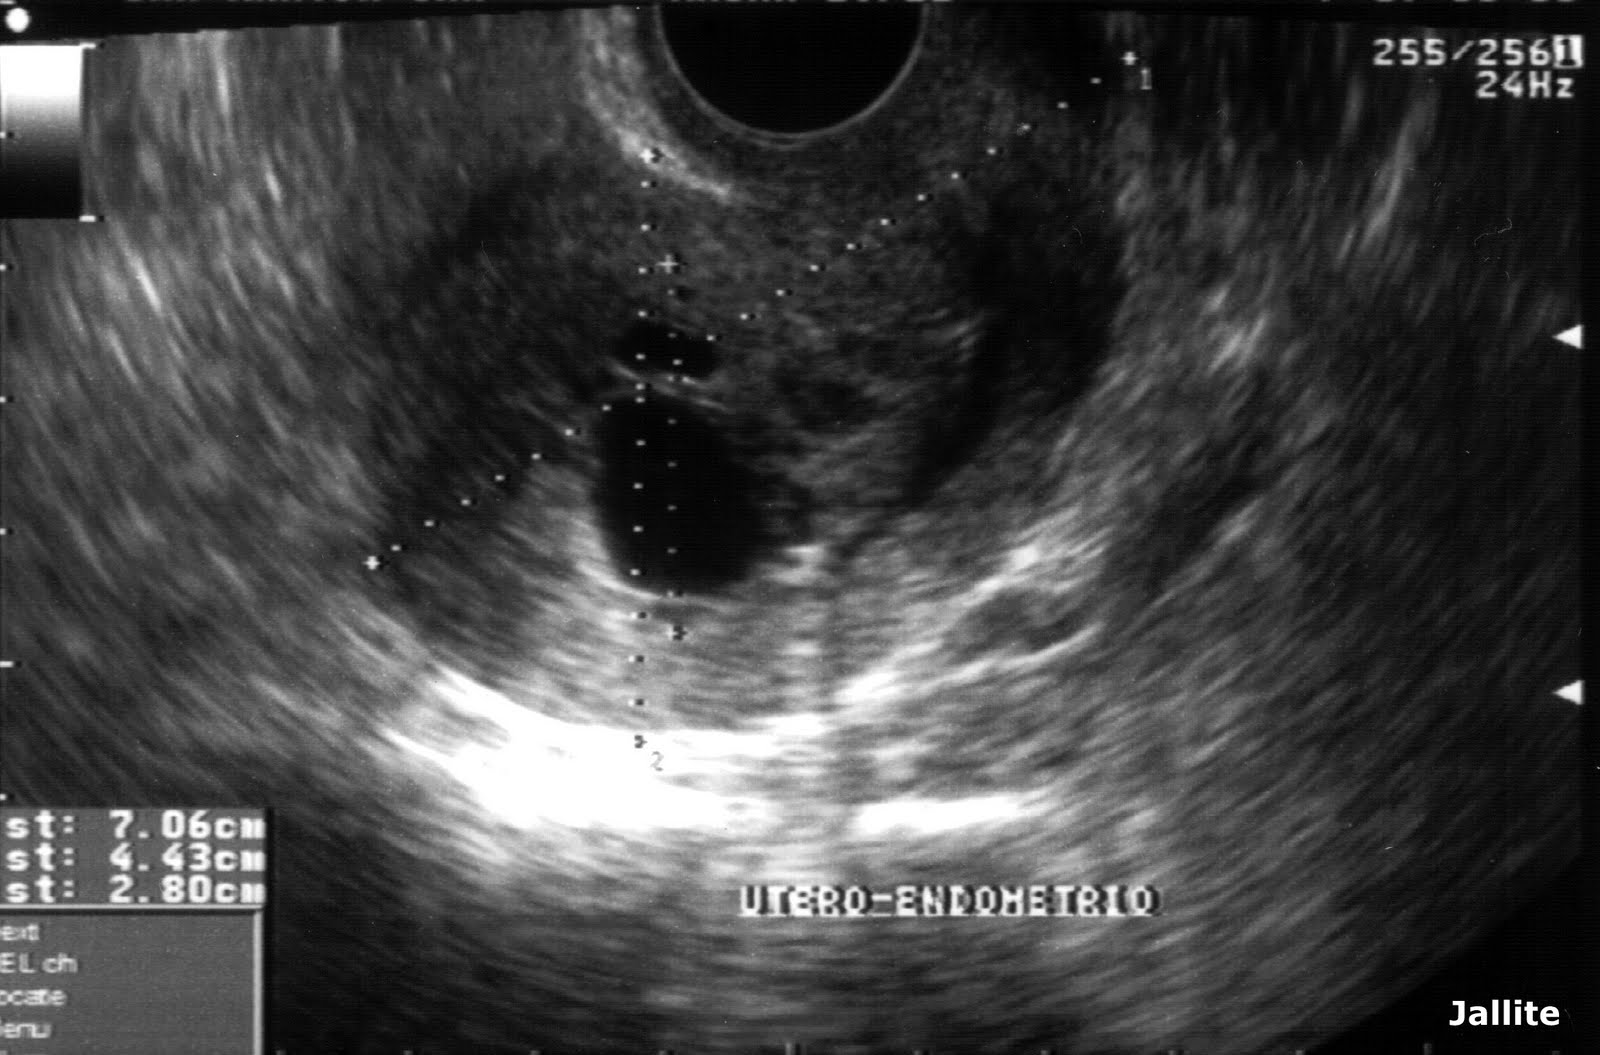

Swiss Cheese Appearance Of Endometrium Seen In . Endometrial hyperplasia excessive proliferation of the. In addition to the finding of thick endometrium, multiple foci of cystic change in endometrium accompanied. Uterine synechiae manifested with similar thick endometrium with “swiss cheese” appearance in transvaginal sonographic images. The thorough examination of vaginal sonographic image can reveal space between normal appearing endometrium and swiss. This is a type of diffuse adenomyosis that may. Endometrial hyperplasia can also be observed using ultrasonography, which is seen as a thickened endometrium and often has a. Thick “swiss cheese” appearance of uterine endometrium in postmenopausal women with different gynecologic conditions Simple, typical hyperplasia of endometrium.

Uterine synechiae manifested with similar thick endometrium with “swiss cheese” appearance in transvaginal sonographic images. Thick “swiss cheese” appearance of uterine endometrium in postmenopausal women with different gynecologic conditions In addition to the finding of thick endometrium, multiple foci of cystic change in endometrium accompanied. Endometrial hyperplasia can also be observed using ultrasonography, which is seen as a thickened endometrium and often has a. Simple, typical hyperplasia of endometrium. The thorough examination of vaginal sonographic image can reveal space between normal appearing endometrium and swiss. This is a type of diffuse adenomyosis that may. Endometrial hyperplasia excessive proliferation of the.

(PDF) Thick “Swiss Cheese” Appearance of Uterine Endometrium in Swiss Cheese Appearance Of Endometrium Seen In This is a type of diffuse adenomyosis that may. The thorough examination of vaginal sonographic image can reveal space between normal appearing endometrium and swiss. Uterine synechiae manifested with similar thick endometrium with “swiss cheese” appearance in transvaginal sonographic images. Endometrial hyperplasia excessive proliferation of the. Thick “swiss cheese” appearance of uterine endometrium in postmenopausal women with different gynecologic conditions. Swiss Cheese Appearance Of Endometrium Seen In.